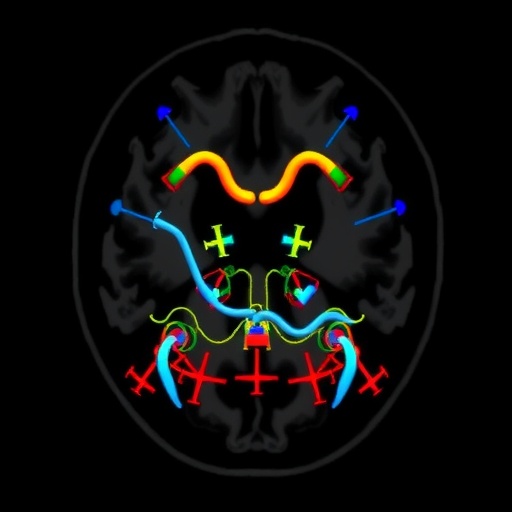

In the case of cervicofacial lymphatic malformations, imaging with MRI allows for a detailed analysis of soft tissue and vascular structures. This clarity is particularly crucial, as many patients may experience not only aesthetic challenges but also functional impairments related to airway or feeding difficulties. The comprehensive nature of MRI images enables healthcare providers to devise surgical and non-surgical interventions ideally suited for reducing complications and enhancing overall quality of life.

The researchers also explore how advancements in MRI technology have made it more accessible and practical for routine use. Contemporary MRI techniques, such as diffusion-weighted imaging and dynamic contrast-enhanced studies, provide more comprehensive insights into the vascularity and tissue characteristics of lymphatic malformations. These innovations enable practitioners to make informed decisions not only about immediate treatment but also about long-term patient management strategies.